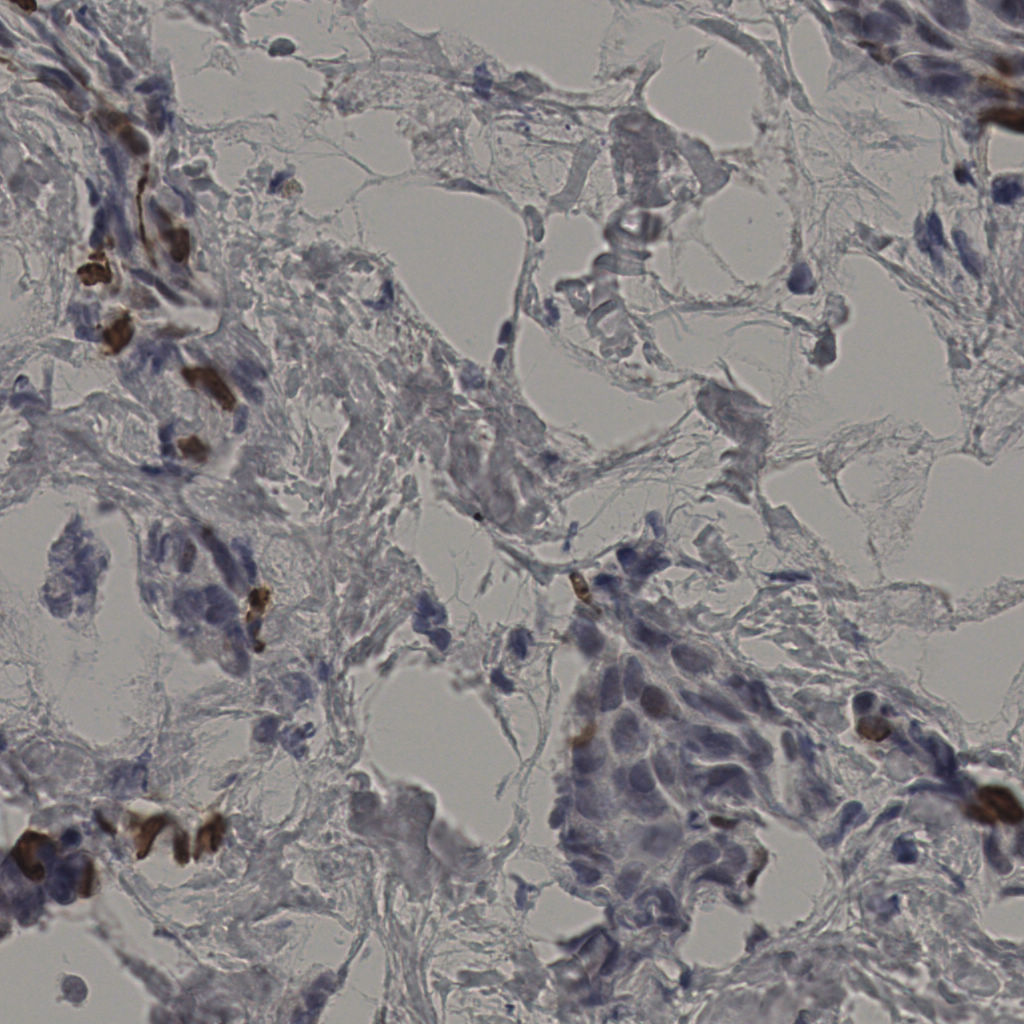

5.31%

Ki67 指数

阴 19502 阳 1093

20240398Ki-67.ndpi

slice_34_10_x30464_y8960.png

slice_34_10_x3046...